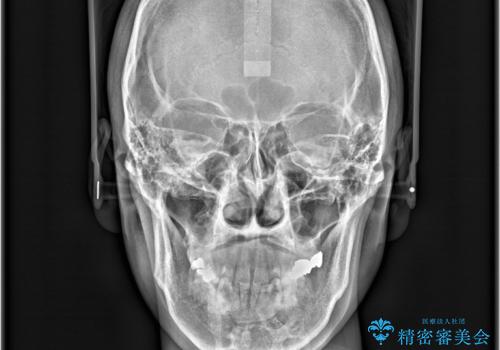

- 前歯の隙間と歯のデコボコを主訴にご来院された患者様です。

加えて、上下の奥歯が全く咬み合わないシザーズバイトの状態も認められました。

矯正検査の結果、非抜歯でインビザラインによる治療が可能と判断し、治療を行いました。